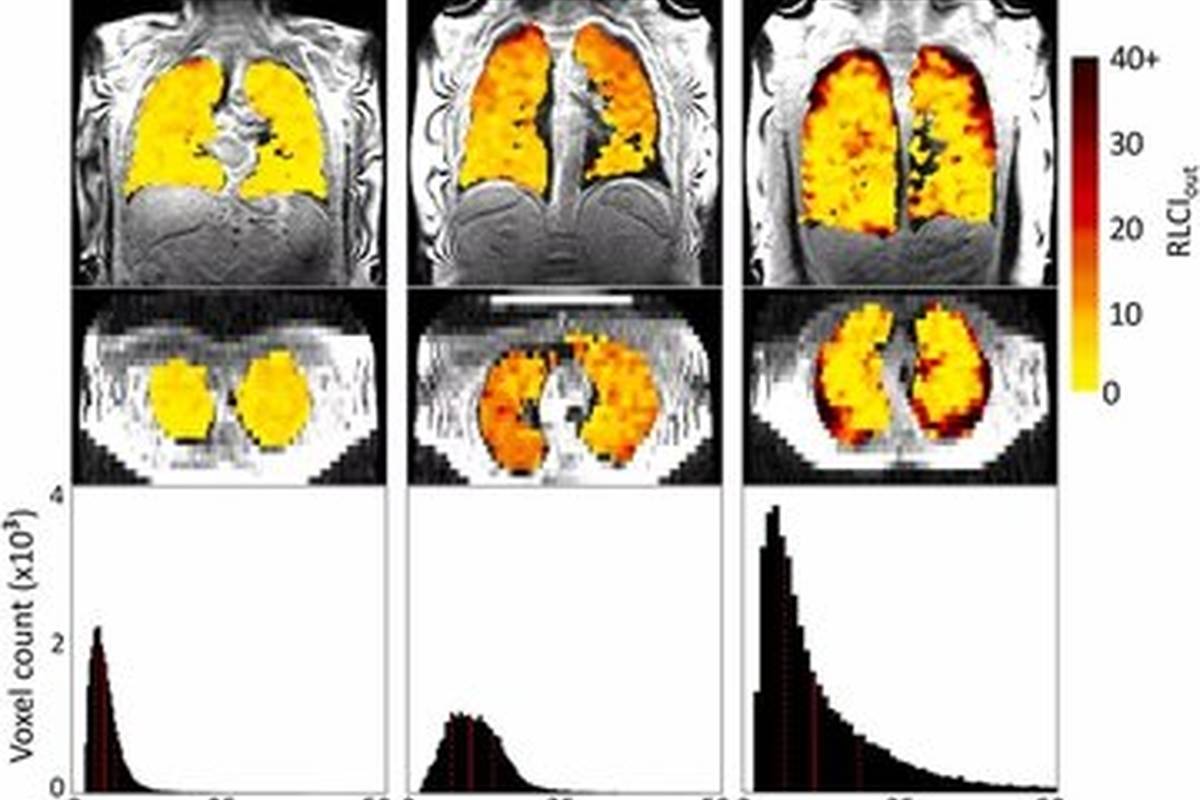

محققان دانشگاه نیوکاسل انگلستان، موفق شدند که نحوه جابهجایی هوا در ریه افراد مبتلا به بیماریهای تنفسی مثل آسم، بیماری مزمن انسدادی ریه و دریافتکنندگان پیوند ریه را بهثبت برساند. آنها به این منظور از گاز خاصی به نام پرفلوئوروپروپان استفاده کردند که با استفاده از یک دستگاه MRI قابل ردیابی است. بیماران میتوانند بدون هیچ مشکلی اقدام به تنفس این گاز بیضرر کنند و سپس اسکنر، مسیر حرکت گاز در ریه آنها را آشکار سازد.

پروفسور «پیت تلوالیس» که سرپرست این پژوهش بوده است، میگوید: اسکنهای ما میتواند نواحی دارای مشکل در تهویه داخل ریه افراد مبتلا به بیماریهای تنفسی را نشان دهد. همچنین میتوان فهمید که کدام یک از بخشهای ریه در طی روند درمان، بهبود پیدا کردهاند. برای مثال وقتی ریه بیمار مبتلا به آسم را با این تکنیک بررسی میکنیم، قادر هستیم از مسیر ورود و خروج هوا بفهمیم که کدام قسمتها عملکرد بهتری را نسبت به گذشته کسب کردهاند.

یکی دیگر از کاربردهای بالقوه تکنیک تصویربرداری مذکور، تشخیص زودهنگام مشکلات ریه در افرادی است که پیوند ریه دریافت کردهاند. پس زدن بافت پیوندی توسط سیستم ایمنی فرد دریافتکننده، یکی از مشکلات رایجی است که بیماران تحت پیوند با آن مواجه میشوند. پژوهشگران ثابت کردهاند که در طی این فرایند، مسیرهای هوایی کوچک در ریه آسیب میبینند و نرخ جابهجایی گازها در آنها کاهش پیدا میکند. محققان امیدوارند با تشخیص زودهنگام، بتوانند از پس زدن بافت پیوندی جلوگیری بهعمل آورند.